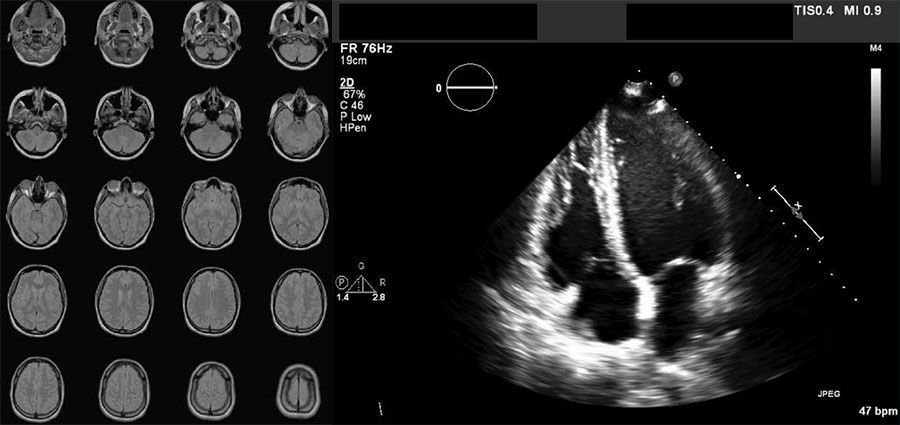

MR image series of a brain (left) and a cardiac ultrasound scan (right) stored in DICOM format.

DICOM, which stands for Digital Imaging and Communications in Medicine, is an international standard for storing, transmitting, and managing medical imaging information and related data. It ensures interoperability between different imaging devices and systems, such as MRI, CT, ultrasound, and X-ray machines, by standardizing the format of images and the communication protocols used to share them. DICOM files typically include both the image data and important metadata—such as patient information, imaging parameters, and study details—making it essential for efficient and accurate diagnosis, treatment planning, and archiving in healthcare environments.

The DICOM data format efficiently stores and transmits medical images and associated metadata in a standardized file. Each DICOM file contains data elements organized hierarchically, including tags, data types, lengths, and values. DICOM encapsulates image data, such as CT, MRI, ultrasound, or X-ray scans, alongside metadata, such as patient ID, acquisition settings, and timestamps. Unlike general-purpose image formats such as JPEG and PNG, DICOM is specifically designed for medical use, supporting multiframe images, 3D volumes, and integration with hospital information systems. Enhanced DICOM is an advanced version, better supporting modern imaging technologies and complex clinical workflows and making it crucial for clinical accuracy and interoperability.